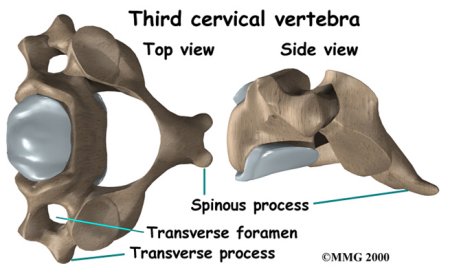

The cervical spine is formed by the first seven vertebrae. Doctors often refer to these vertebrae as C1 to C7. The cervical spine starts where the top vertebra (C1) connects to the bottom edge of the skull. The cervical spine curves slightly inward and ends where C7 joins the top of the thoracic spine. This is where the chest begins.

Each vertebra is formed by a round block of bone, called a vertebrae body. A bony ring attaches to the back of the vertebral body. When the vertebrae are stacked on top of each other, the rings form a hollow tube. This bony tube surrounds the spinal cord as it passes through the spine. Just as the skull protects the brain, the bones of the spinal column protect the spinal cord.

Vertebrae Body

Bony Ring

Bony Ring

One way to understand the anatomy of the cervical spine to look at a spinal segment. Each spinal segment includes two vertebrae separated by an intervertebral disc, the nerves that leave the spinal cord at that level, and the small facet joints (described later) that link each level of the spinal column.

There are two facet joints between each pair of vertebrae, one on each side of the spine. A facet joint is made up of small, bony knobs that line up along the back of the spine. Where these knobs meet, they form a joint that connects the two vertebrae. The alignment of the facet joints of the cervical spine allows freedom of movement as you bend and turn your neck.

Two spinal nerves exit the sides of each spinal segment, one on the left and one on the right. As the nerves leave the spinal cord, they pass through a small bony tunnel on each side of the vertebra, called a neural foramen. (The term used to describe more than one opening is neural foramina.)